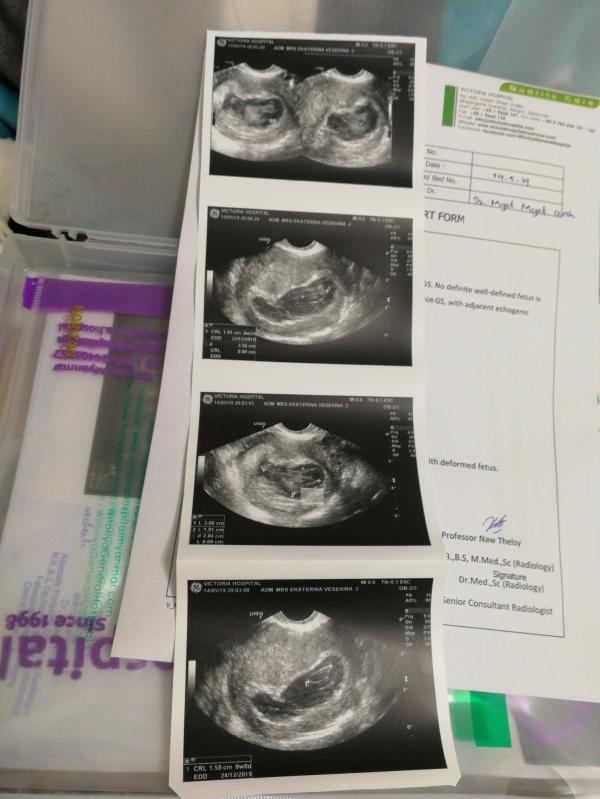

Девочки, SOS! Сделала УЗИ, я в шоке! В заключении написано деформирован плод. Это что ещё за новости? Ставили такой диагноз кому нибудь? С каждой беременностью все новые фишки, сколько это можно ещё терпеть? Может есть у кого знакомые врачи, с кем можно посоветоваться?